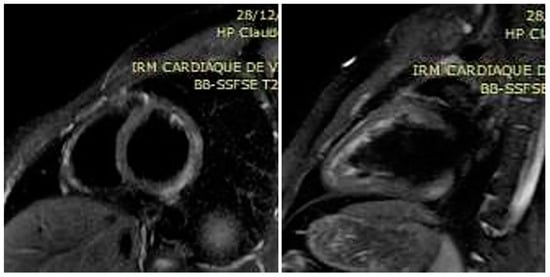

Figure 1. Black-blood edema-sensitive T2 STIR images showing subepicardial posterolateral hypersignal (arrows) indicative of focal edema in the short axis and the 2-chamber view of the left ventricle.

A 23-year-old male patient without past medical history presented to the emergency room with recent retrosternal chest tightness and pain. He reported recent gastro-intestinal (GI) symptoms of nausea, vomiting, 4-day watery diarrhea with transient episode of fever (38.7 °C). At admission, physical examination showed an impaired general status. He was afebrile (37.2 °C), respiratory rate 20 per min., cardiac assessment showed blood pressure of 140/70 mmHg, regular tachycardia of 100 beats per minute and normal cardiac murmur. Pulmonary examination showed a respiratory rate of 16 cycles per min, and auscultation was normal. He denied abdominal pain, and palpation showed no tenderness and no liver or spleen enlargement. He reported generalized myalgia but rheumatological evaluation did not show arthritis or productive myalgia. The electrocardiogram (ECG) showed left axis deviation with regular sinusal tachycardia. Routine laboratory showed leukocytosis 13 G/L (normal range < 10 G/L), neutrophilia 8.2 G/L (normal range 1.5–7 G/L) and lymphopenia 600/mm3 (normal range 1500 to 4000/mm3) on cell blood count, with elevated C-reactive protein of 130 mg/dL (normal range < 5 mg/dL), serum electrolytes, creatinine and liver enzymes within normal limits. Maximum Troponins and creatine kinase MB (CK-MB) were elevated to 678 ng/L (normal range < 14 ng/L) and 54 ng/mL (normal range < 7 ng/mL). The patient was admitted to the cardiac department for further workup. He was managed symptomatically with analgesics, anti-reflux and fluids. Transthoracic echocardiography (TTE) revealed a preserved ejection fraction (EF) of 55% with normal wall motions, no valvular dysfunction, normal pulmonary pressure and no pericardial effusion. His risk of coronary artery disease (CAD) was low; moreover, clinical, biological and echocardiographic presentation summed the hypothesis of an acute myocarditis. A large etiological workup, including repeated peripheral blood culture, Mycoplasma pneumoniae, Chlamydia pneumoniae, Coxiella burnetii, Borrelia burgdorferi, Leptospira spp., Rickettsia spp. and Brucella spp., was conducted. The serologies, such as urinary Legionella pneumophila antigen, were negative. Moreover, serologies of RNA viruses (coxsackieviruses A and B, hepatitis C virus, human immunodeficiency virus) and DNA viruses (adenoviruses, parvovirus B19, cytomegalovirus, human herpes virus-6, Epstein-Barr virus, varicella-zoster virus and herpes simplex virus) were negative. Autoimmune assessment, including antinuclear, anti-neutrophil cytoplasmic antibodies, systemic sclerosis and autoimmune myopathies specific antibodies and converting enzyme assay, were negative. The patient denied any recent drug intake. A Gram stain of specimen stool collected showed multiple curved and spiral Gram-negative rods. Biochemical tests indicated an oxidase, catalase and hippurate negative and indoxyl acetate-positive bacterial species, corresponding to C. jejuni. Stool cultures confirmed the diagnosis of C. jejuni sensitive to macrolides (Azithromycin/Roxithromycin/Clarythromycin) and flouroquinolones (Ciprofloxacin). Continuous telemetry monitoring showed some runs of non-sustained ventricular tachycardia (NSVT). Oral bisoprolol 2.5 mg twice daily was started for that, and oral 1 g of Azithromycin was administered. He remained clinically stable over the rest of the hospital course, and the diarrhea was progressively resolved. The patient remained stable, and we could perform cardiovascular magnetic resonance (CMR) imaging. Triple inversion-recovery black-blood T2-weighted STIR sequences showed focal areas of hypersignal in the subepicardium of the posterolateral left ventricular (LV) wall, indicative of myocardial edema (Figure 1). In addition, steady-state-free-precession (SSFP) cine CMR showed early hypersignal in the subepicardium of the posterolateral LV wall immediately after injection of 0.1 mM of Gadolinium chelates, indicating focal hyperemia (Figure 2). Inversion-recovery gradient-echo-based late Gadolinium enhancement techniques, acquired 10 min. after Gadolinium injection, revealed subepicardial nodular lesions of myocardial damage (Figure 3). The final diagnosis of C. jejuni-related acute myocarditis was supported by the Lake Louise criteria [7]. The patient was discharged free of symptoms after one week in hospital. On close follow-up, his C-reactive protein and cardiac enzymes normalized after three weeks. Repeated TTE and 24-h ECG were normal, so bisoprolol was progressively discontinued after 6 months. Control CMR imaging at 3 months showed regression of the focal areas of hyper signal in the sub epicardium of the posterolateral left ventricular (LV) wall.